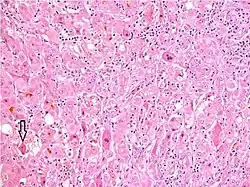

Hepatitis can also occur in neonates and is attributable to a variety of causes, some of which are not typically seen in adults.[56] Congenital or perinatal infection with the hepatitis viruses, toxoplasma, rubella, cytomegalovirus, and syphilis can cause neonatal hepatitis.[56] Structural abnormalities such as biliary atresia and choledochal cysts can lead to cholestatic liver injury leading to neonatal hepatitis.[56] Metabolic diseases such as glycogen storage disorders and lysosomal storage disorders are also implicated.[56] Neonatal hepatitis can be idiopathic, and in such cases, biopsy often shows large multinucleated cells in the liver tissue.[57] This disease is termed giant cell hepatitis and may be associated with viral infection, autoimmune disorders, and drug toxicity.[58][59]